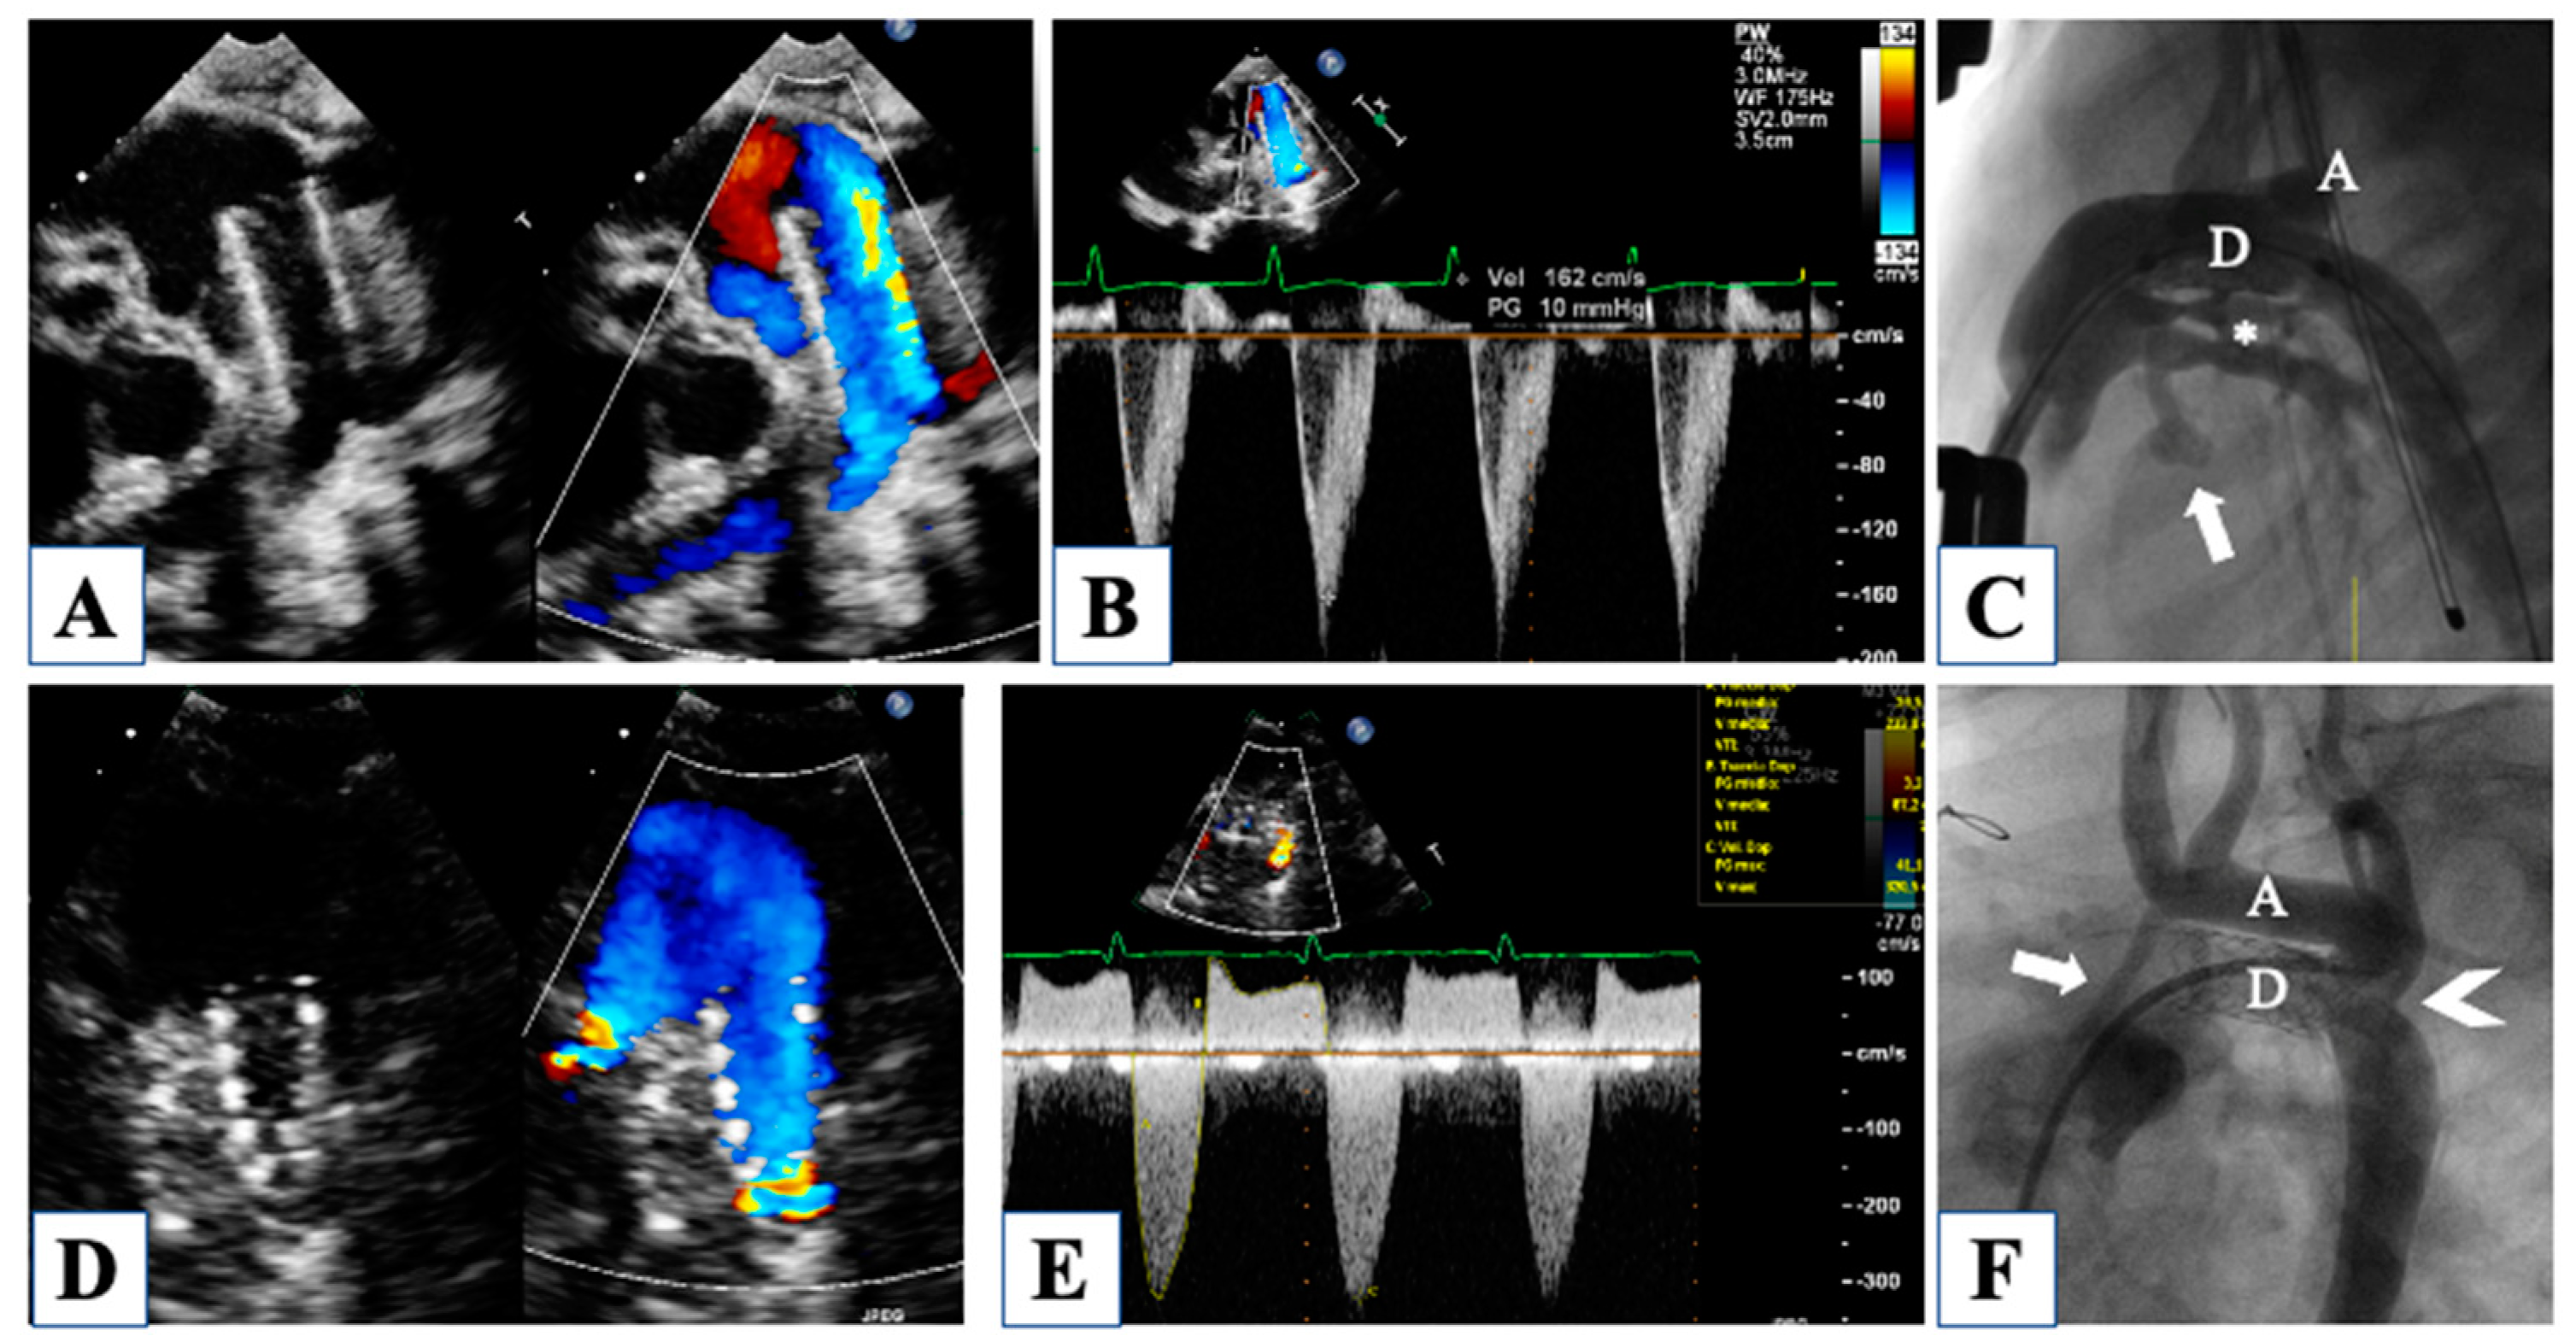

| Fenstermaker et al., 2008 | [17] | Interstage I–II | Pulmonary arteries flow velocity, pulsatility index, and systolic/diastolic ratio; | CW Doppler on pulmonary arteries | Correlation with ASD restriction, ductal obstruction, aortic arch obstruction |

| ASD mean gradient, ductus arteriosus peak velocity, retro-aortic arch peak velocity | CW Doppler through ASD, ductus and aortic arch | ||||

| Egan et al., 2011 | [18] | Interstage I–II | Smaller aortic root, higher flow velocity from the retrograde aortic arch | Linear measurement of aortic root, CW Doppler through the retrograde aortic arch | Prediction of retrograde aortic arch obstruction |

| Birnbaum et al., 2010 | [19] | Interstage-stage II | Retrograde ductal VTI, RV FAC | CW Doppler through the ductus, RV area change | Correlation with peri-operative cardiac output |